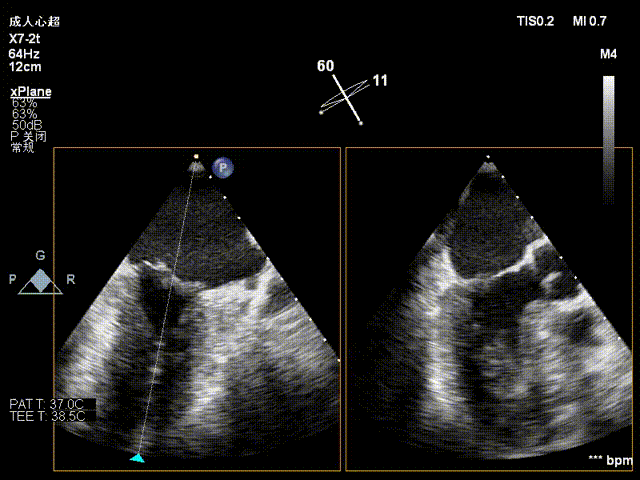

患者取平卧位,消毒铺巾后,穿刺右股静脉后置入6F血管鞘,经食道超声指导下进行房间隔穿刺,穿刺高度约4cm。

房间隔穿刺高度4cm

房间隔穿刺

NeoNova®C6(宽6mm)夹合器沿输送系统进入左房,调整夹合器orientation,夹合器抵达3区反流处。

进夹合器

进夹合器调弹道